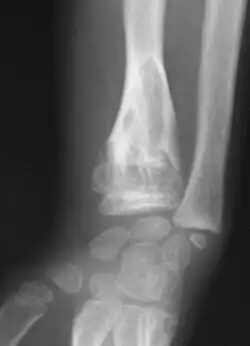

-

X-ray showing calcified enchondromas localized in finger a 37-year-old patient affected with Ollier disease -

X-ray showing enchondromas localized in the humerus of a 37-year-old patient affected with Ollier disease -

X-ray showing enchondromas localized in the lower part of the radius of a 37-year-old patient affected with Ollier disease -